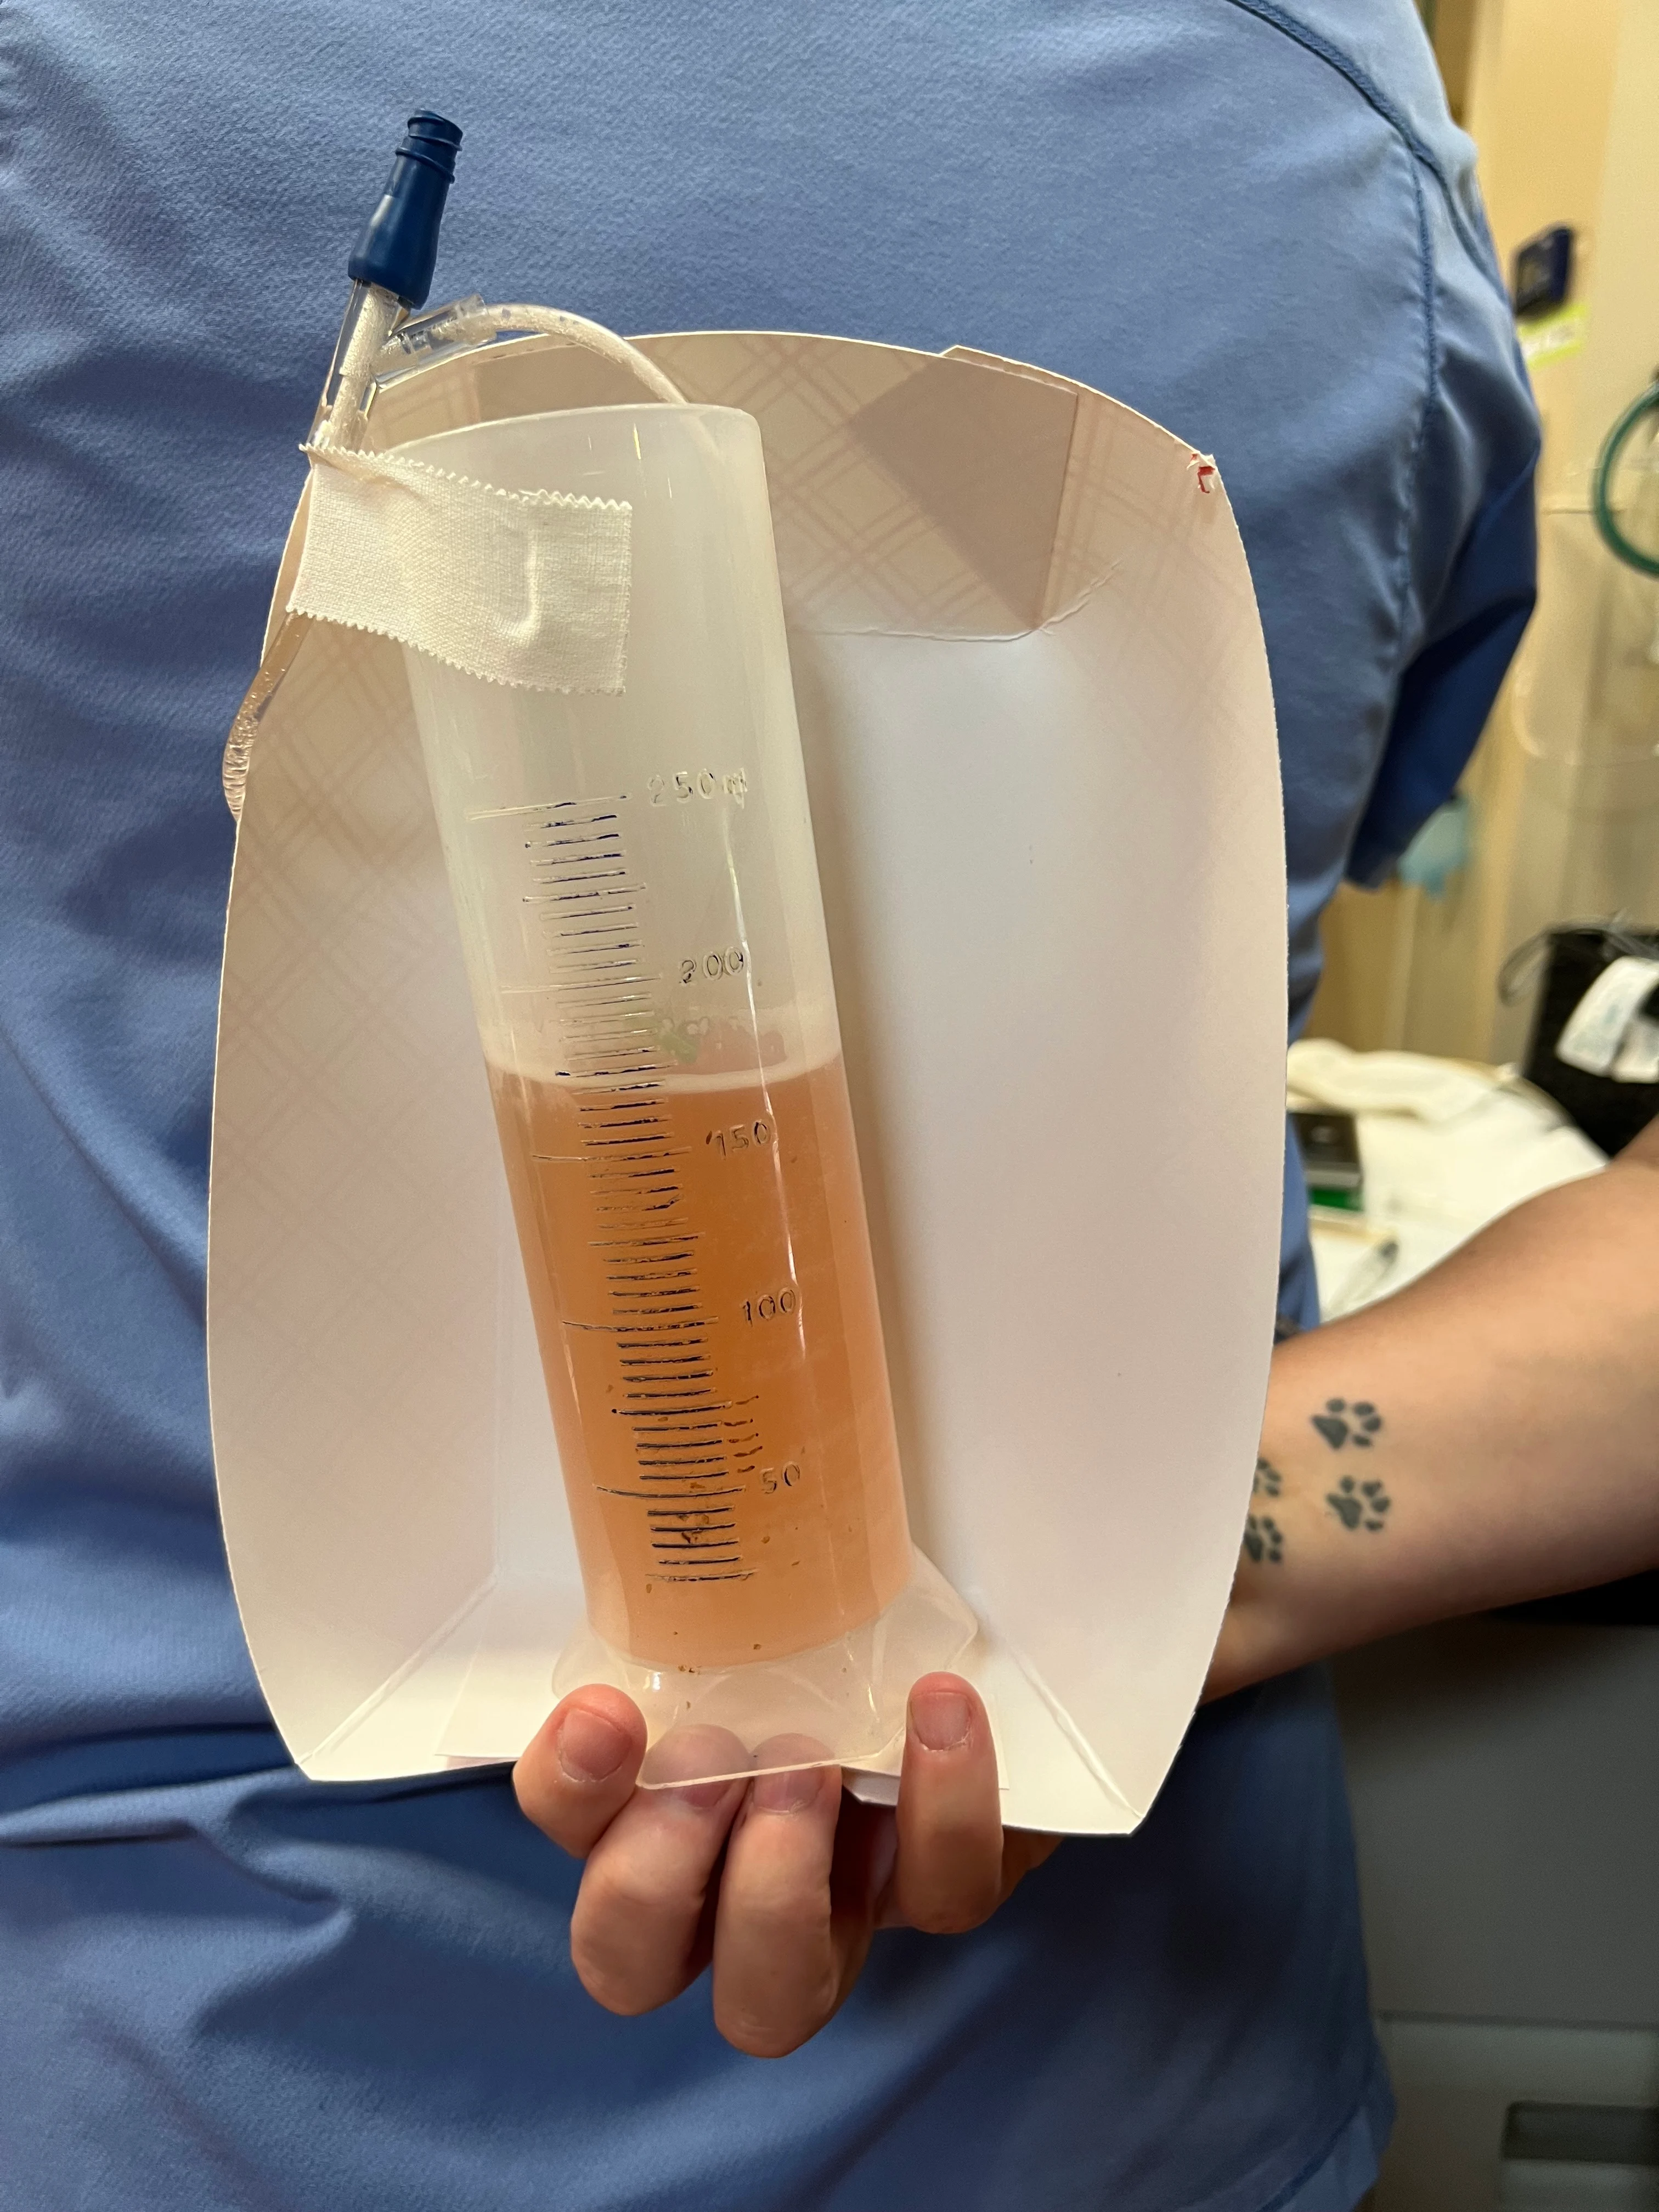

Turn the stopcock so it is open to the patient. Apply gentle negative pressure to the syringe, and allow fluid to fill the syringe. Once the syringe is full, turn the stopcock off to the patient and open to the collection container for evacuation. Repeat this process until negative pressure is obtained and the pleural effusion is removed. Save samples in lavender-top and nonadditive tubes for analysis. If pyothorax is suspected, also save a fluid sample for culture and susceptibility testing.

Unilateral or bilateral drainage may be required. The volume removed from each hemithorax should be quantified and described.